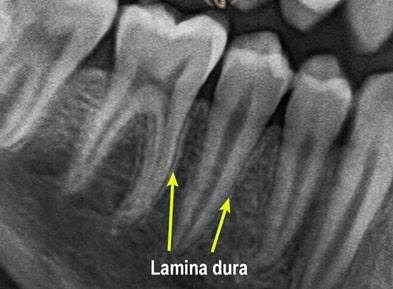

Lamina dura (LD) is a radiographic landmark viewed largely on periapical radiographs (PR). The terminology LD (or alveolus) is applied to the thin layer of dense cortical bone, which lines the roots of sound teeth. Presence of LD is an indication of the health of the teeth.